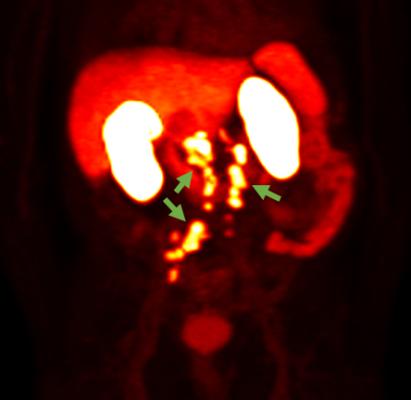

An oral presentation on the investigational radiohybrid Prostate-Specific Membrane Antigen (rhPSMA) compound, 18F-rhPSMA-7.3, is being made at the conference. It includes additional results from the Company’s Phase 3 SPOTLIGHT study (NCT04186845) evaluating the impact of clinical factors on the detection rate of 18F-rhPSMA-7.3 PET imaging in men with suspected prostate cancer recurrence based on elevated PSA following prior therapy. Presentations on studies of Axumin (fluciclovine F 18) include interim analyses from a randomized trial of 18F-fluciclovine and 68Ga-PSMA PET/CT in post-prostatectomy radiotherapy, experience on the prognostic utility of 18F-fluciclovine PET after salvage radiotherapy, and timing and patterns of potentially salvageable recurrences after SBRT for localized prostate cancer. Additionally, the Company will host an Industry-Expert Theater event, “Emerging Data on the Impact of Axumin® (fluciclovine F 18) PET Imaging on Radiotherapy Decisions.” Details of selected oral and poster presentations by Blue Earth Diagnostics and its collaborators are listed below.

1049 Impact of Clinical Factors on 18F-rhPSMA-7.3 Detection Rates in Men with Recurrent Prostate Cancer: Findings from the Phase 3 SPOTLIGHT Study |

Axumin (fluciclovine F 18) injection is indicated for positron emission tomography (PET) imaging in men with suspected prostate cancer recurrence based on elevated blood prostate specific antigen (PSA) levels following prior treatment.